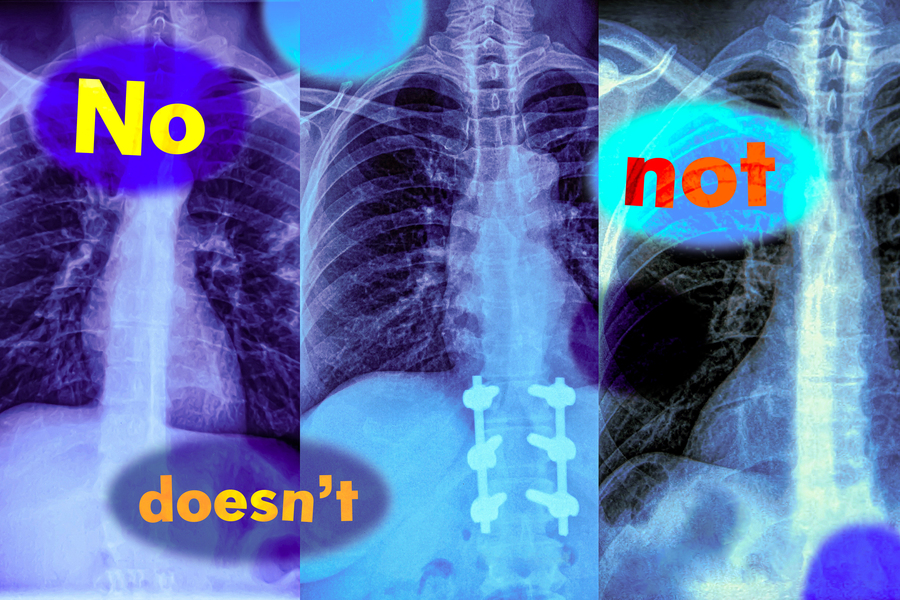

MIT researchers found that vision-language models, which are widely used to analyze medical images to streamline diagnosis, do not understand negation words like “no” and “not” (Credits: iStock; MIT News).

In a new study, MIT researchers have found that vision-language models are extremely likely to make such a mistake in real-world situations because they don’t understand negation — words like “no” and “doesn’t” that specify what is false or absent.